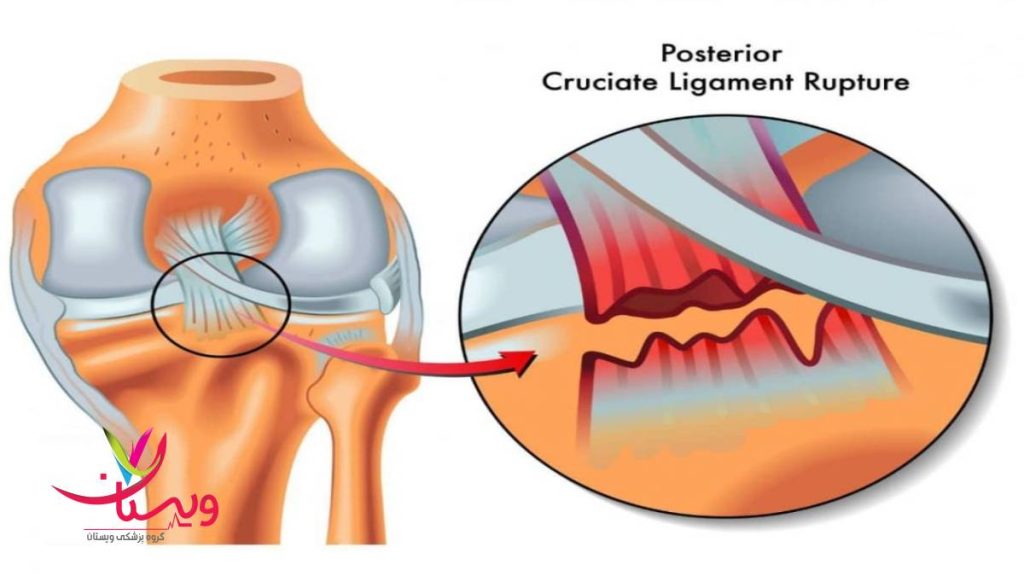

تست پارگی رباط صلیبی

تست پارگی رباط صلیبی یکی از روشهای کلیدی برای تشخیص آسیبهای زانو بهویژه در ورزشکاران و افرادی است که دچار پیچخوردگی یا ضربه شدید به مفصل زانو شدهاند. رباط صلیبی جلویی (ACL) و رباط صلیبی خلفی (PCL) نقش مهمی در پایداری و حرکت طبیعی زانو دارند. در صورت آسیبدیدگی این رباطها، فرد دچار درد، تورم، ناپایداری و کاهش توان حرکتی میشود.

How are cruciate ligaments injured?

The anterior cruciate ligament (ACL) is one of the most common ligaments to be injured. The ACL is often stretched and/or torn during a sudden twisting motion (when the feet stay planted one way, but the knees turn the other way). Skiing, basketball, and football are sports that have a higher risk of ACL injuries.The posterior cruciate ligament (PCL) is also a common ligament to become injured in the knee. However, the PCL injury usually occurs with sudden, direct impact, such as in a car accident or during a football tackle.

رباط های صلیبی چگونه آسیب می بینند؟

رباط صلیبی قدامی (ACL) یکی از شایع ترین رباط هایی است که آسیب می بیند. ACL اغلب در طول یک حرکت چرخشی ناگهانی کشیده می شود و/یا پاره می شود (زمانی که پاها به یک طرف کاشته می شوند، اما زانوها به سمت دیگر می چرخند). اسکی، بسکتبال و فوتبال ورزش هایی هستند که خطر آسیب دیدگی ACL در آنها بیشتر است.رباط متقاطع خلفی (PCL) نیز یک رباط متداول برای آسیب دیدگی در زانو است. با این حال، آسیب PCL معمولاً با ضربه مستقیم و ناگهانی مانند تصادف رانندگی یا در حین تکل فوتبال رخ می دهد.